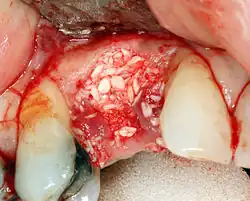

Additional procedures to augment deficient bone in implant site

For an implant to osseointegrate, it needs to be surrounded by a healthy quantity of bone. In order for it to survive long-term, it needs to have a thick healthy soft tissue (gingiva) envelope around it. It is common for either the bone or soft tissue to be so deficient that the surgeon needs to reconstruct it either before or during implant placement.[50]: 1084 All techniques of augmenting the alveolar bone in preparation for implant placement are invasive and associated with a degree of morbidity.[59]

Hard tissue (bone) reconstruction

Bone grafting is necessary when there is a lack of bone. It also helps to stabilize the implant by increasing survival rates of the implant and decreasing marginal bone level loss.[60] While there are always new implant types, such as short implants, and techniques to allow compromise, a general treatment goal is to have a minimum of 10 mm (0.39 in) in bone height, and 6 mm (0.24 in) in width. Alternatively, bone defects are graded from A to D (A=10+ mm of bone, B=7–9 mm, C=4–6 mm and D=0–3 mm) where an implant's likelihood of osseointegrating is related to the grade of bone.[61]: 250

To achieve an adequate width and height of bone, various bone grafting techniques have been developed. The most frequently used is called guided bone graft augmentation where a defect is filled with either natural (harvested or autograft) bone or allograft (donor bone or synthetic bone substitute), covered with a semi-permeable membrane and allowed to heal. During the healing phase, natural bone replaces the graft, forming a new bony base for the implant.[56]: 223